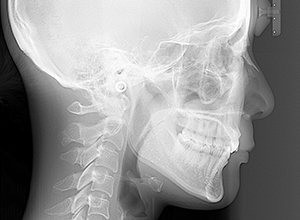

X-Ray

X-Ray所見

セファロ所見 Or-R平面からRは上方に位置づいている。中顔面部の奥行きはあるもののNasionからA点までは距離があるため、下顎は後下方へ回転している。